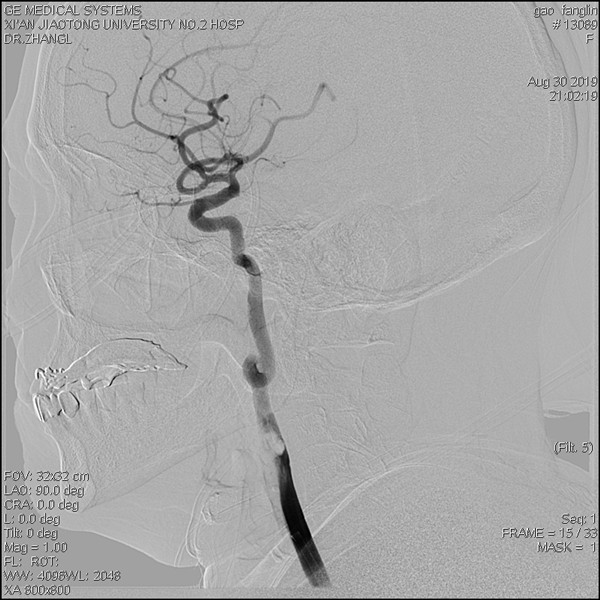

张主任跟随患者救护车,并与家属沟通进一步的诊疗计划,认为患者已在外院溶栓效果不佳,建议尽快行全脑血管造影术,必要时行动脉取栓术。征得家属同意,张主任亲自上台,快速完成了脑DSA,发现右侧颈内动脉虽然再通,但是血管开口有巨大的血栓,随时有脱落引起血管再闭塞的风险,张主任果断决定立即取栓,约10分钟后成功取栓,开通了闭塞的大血管,术后患者左侧肢体肌力立即好转为3级以上。

造影见右侧颈内动脉起始段内大量血栓